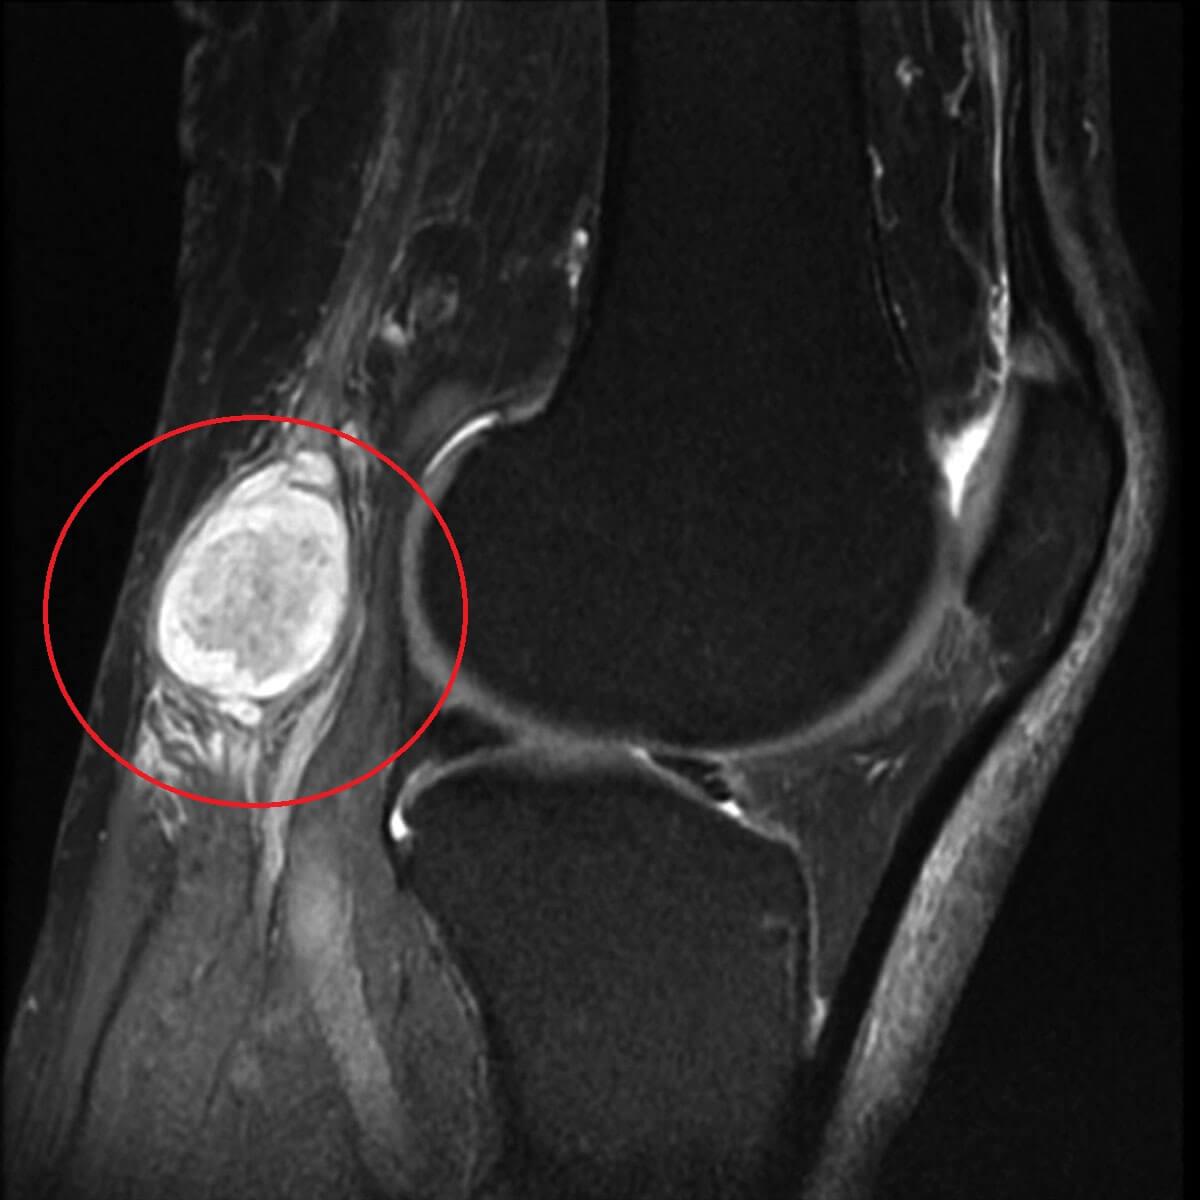

При осмотре и пальпации можно заметить мягкую болезненную опухоль, которая может достигать 7 см в диаметре.

Фото кисты Бейкера под коленом наглядно иллюстрирует, каких размеров может достигать эта киста.